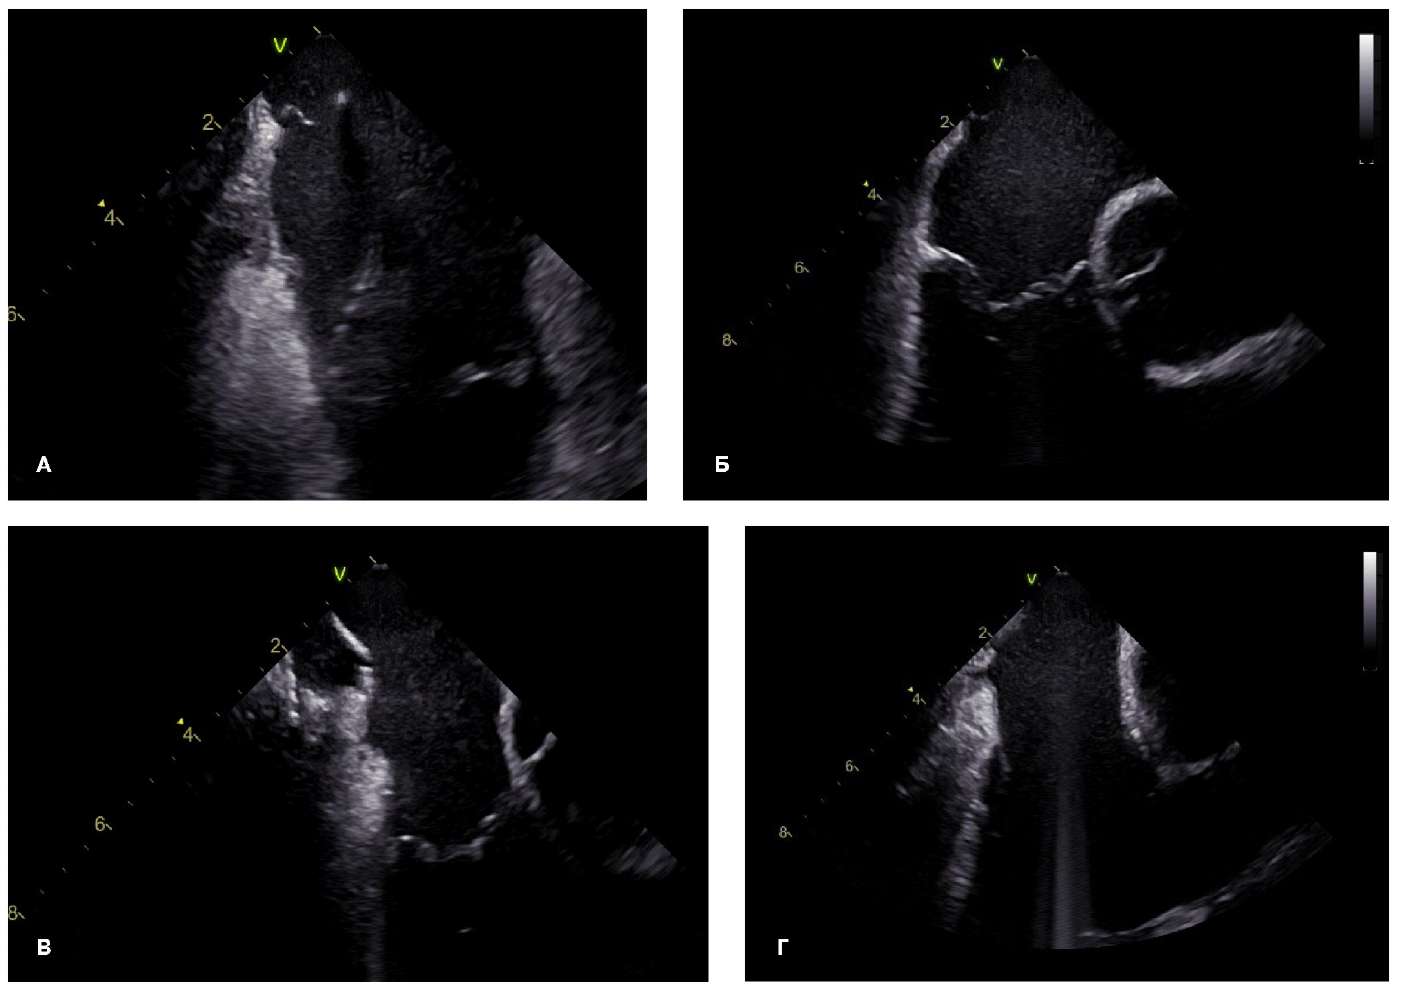

Рис. 1. Полиморфизм центральной части КТП.

У 5 (9,3%) пациентов отмечались затруднения при позиционировании аблационного катетера и достижения блокады проведения по причине наличия углубления/»кармана» КТП: у 3 пациентов (5,6%) — в средней части КТП (при этом наблюдалась наименьшая толщина КТП в этой зоне (до 2,2 мм); у 2 (3,7%) пациентов — в дистальной части КТП перед евстахиевым клапаном, глубиной до 7 мм (рис. 1, В, Г).

На панелях А, Б визуализируется утолщение эндокарда на протяжении перешейка с участком резкого истончения тканей в центральной части. Подобные участки, не визуализирующиеся при рентгеноскопическом подходе, могут подвергаться диссекции при КА, что может приводить к риску перфорации стенки и развитию осложнений.

Панель В — центральная часть перешейка без патологических углублений или дубликатур эндокарда. На панели Г визуализируются углубления («карманы») в центральной и дистальной частях перешейка.